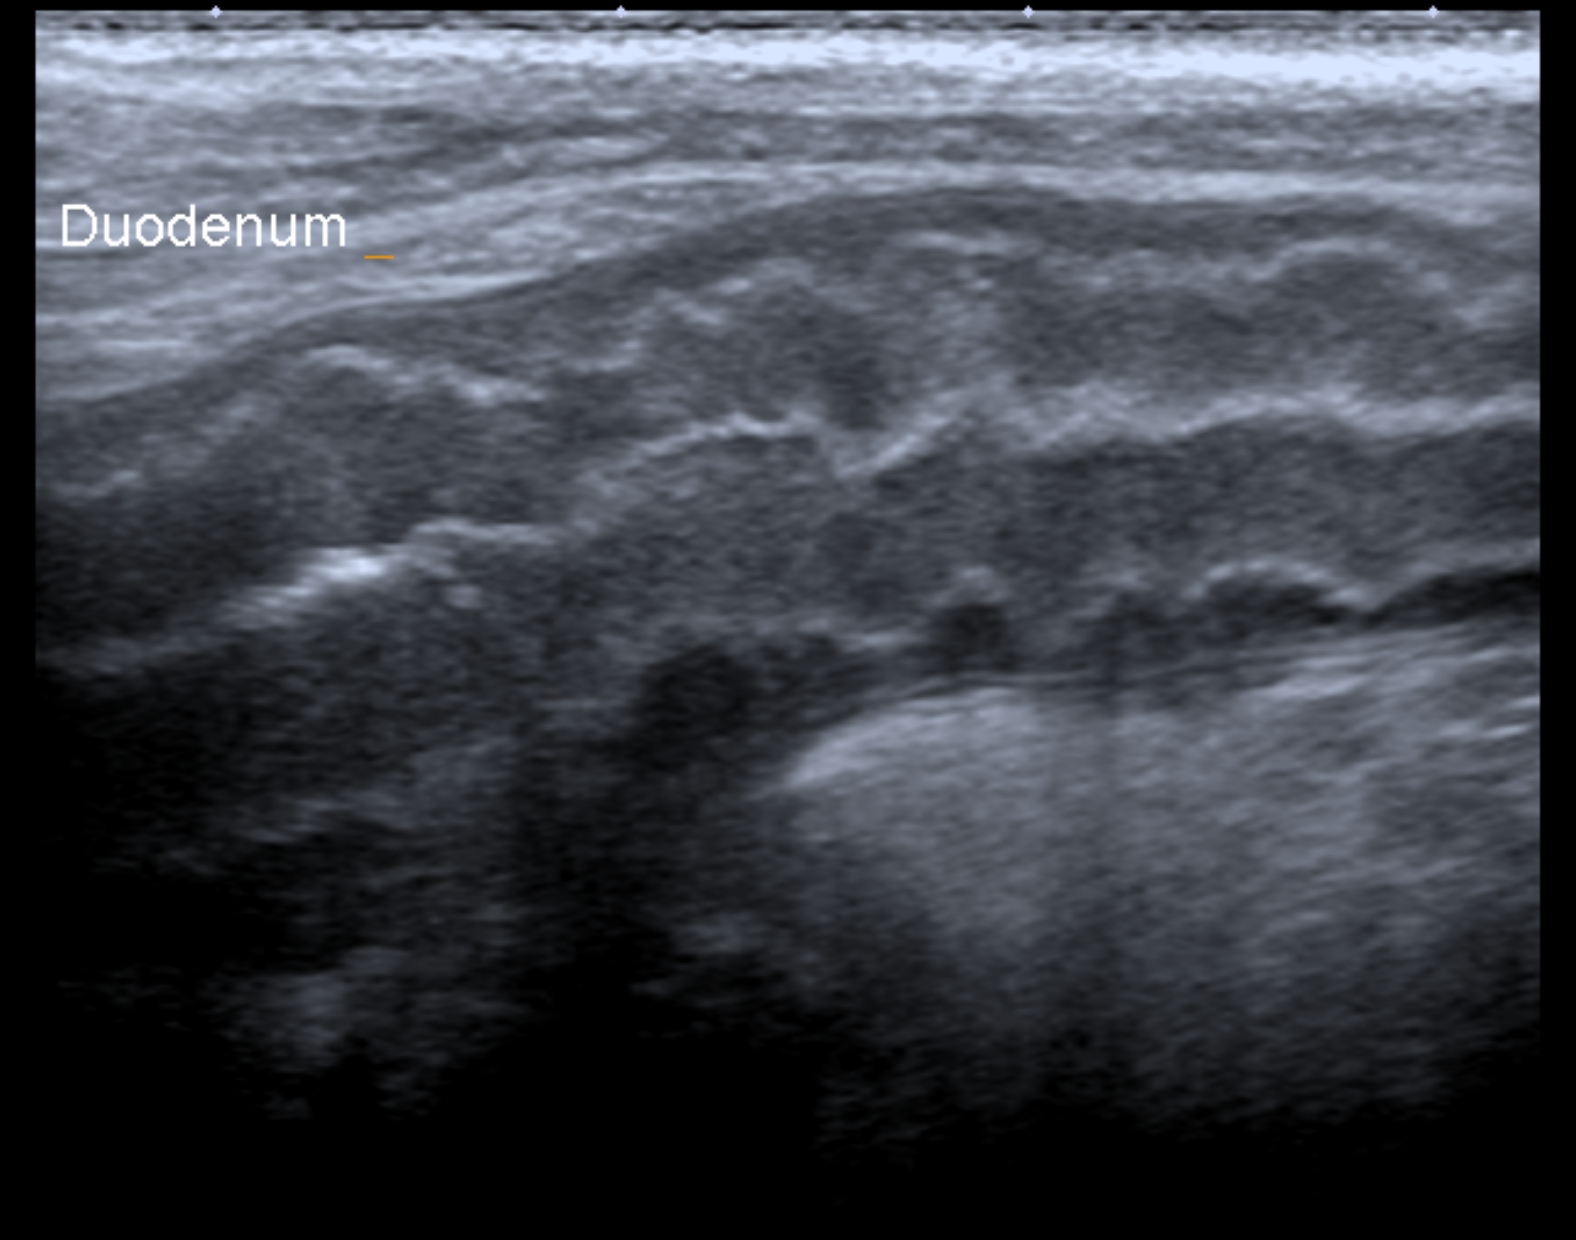

血液検査では膵臓から分泌されるLIP (リパーゼ)値上 昇、炎症があるときに上がるCRPの上昇が見られることが多いです。また、外部への依頼検査で、確定 診断として犬特異的膵リパーゼ(c-PLI)を測定する こともあります。 超音波検査では膵臓の腫大・膵臓周囲の高エコー源 生・十二指腸まで炎症が波及することによる十二指腸のコルゲートサイン(うねうねしてみえる)が指 標となります。

十二指腸のコルゲートサインです。